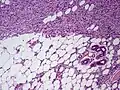

Subcutaneous tissue infiltration (i.e. "honeycomb" growth pattern)